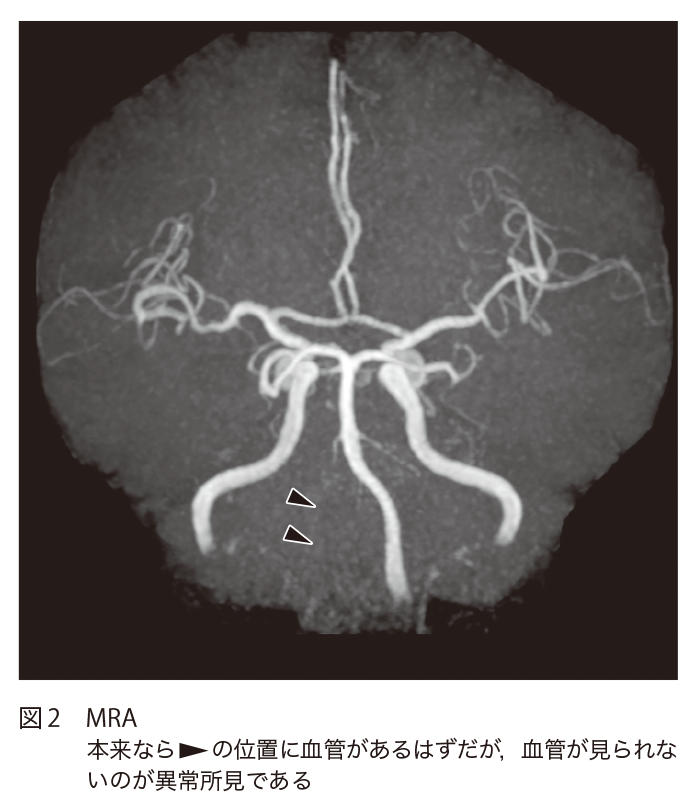

頭痛と歩行障害で救急受診した70歳代男性 70歳代男性,頭痛で近医受診.頭部CTでは異常なしと診断された.翌日より歩行困難と嘔吐が生じたため救急受診し,頭部CTが施行された. A1.椎骨動脈解離による延髄外側梗塞A2.脳外科へのコンサルト 1.診断のポイント 延髄右側に拡散強調像高信号がみられ(図1▶︎)ADC値も低下している(非呈示).急性期梗塞の所見である.MRAでは右の椎骨動脈が全く描出されていないが(図2▶︎),FLAIRでは淡い高信号として描出されており,内部に低信号域がみられる(図3▶︎).同日のCT血管造影では右椎骨動脈は動脈相で淡い造影効果を呈し,内部にflap状の構造がみられる(図4▷).右椎骨動脈解離による延髄梗塞である. 2.鑑別診断1) 延髄に病変をきたすものが鑑別となりうる. 1 梗塞 椎骨動脈解離によらないラクナ梗塞,アテローム血栓性梗塞で延髄梗塞をきたす.アテローム血栓性梗塞は延髄外側よりも内側に起こりやすい. 2 腫瘍 毛様細胞性星細胞腫,血管芽腫や,低悪性度の神経膠腫,神経膠芽腫などが鑑別にあがるが,低悪性度の神経膠腫以外は頻度も少なく,経過も異なる. 3 感染・炎症性疾患 小さな膿瘍が梗塞と紛らわしい場合があるが,稀である.感染性脳炎としてHIV患者におけるサイトメガロウイルス感染,単純ヘルペスウイルス感染で延髄単独病変の報告がある.またADEM(acute disseminated encephalomyelitis:急性散在性脳脊髄炎)が片側性に延髄病変をきたす場合がある.しかし,これらの経過や症状は延髄梗塞とは異なる. 4 脱髄疾患・代謝性疾患など 視神経脊髄炎関連疾患,多発性硬化症の延髄病変が片側性に出現する場合がある.Sjögren症候群,Behçet病,サルコイドーシスも片側に出現する場合がある.ただしこれらも経過や症状は延髄梗塞とは異なると思われる. 5 その他 PRES(posterior reversible encephalopathy syndrome:可逆性後頭葉白質脳症)やAVF(arteriovenous fistula:動静脈瘻)で延髄に病変をきたす場合がある.また,肥大性オリーブ核変性症など類似の画像を呈する. 3.次の一手 脳外科にコンサルトを行う.画像的にはMRI撮像時に3Dグラディエント造影T1強調像が撮像できれば血管内膜のflapや解離腔自体の描出が可能であるが,病歴などから解離や梗塞を疑わなければ咄嗟に判断して造影するのは難しいかもしれない.延髄を含む後方循環系の梗塞は内頸動脈領域の梗塞と比較して発症早期での拡散強調像での偽陰性率が高く2),延髄では24時間以内での偽陰性率が高いとの報告があるため、発症早期に拡散強調像高信号が見られなくても超急性期の延髄梗塞を除外できないので注意しなければならない3,4). 救急医Check Point 脳動脈解離は,欧米では頭蓋外内頸動脈に多く,本邦では頭蓋内椎骨動脈に多い.40〜50歳代の比較的若年者に発生する.最も頻度の高い症状は頭痛,頸部痛で70〜80 %に認められ,椎骨動脈解離では後頭部や項部に限局した痛みがみられる.頭痛の特徴としては,はじめての痛み,顔面痛あるいは頸部痛,片側性,持続性(1カ月以内に寛解)などで,解離に伴う痛みであるにもかかわらず必ずしも突然ではなく緩徐に発症することも多い.頭痛の性状は多岐にわたり日常生活に支障がない程度の場合もあるため,性状のみで一般的な頭痛と区別することは困難である.首を鳴らす,急激に振り向くなどの頸部の回転動作の後に頭痛,頸部痛が発生した場合は椎骨動脈解離を疑うきっかけとなる. 発症様式は「虚血(脳梗塞,TIA)」「出血(くも膜下出血)」「無症状もしくは頭痛のみ」の3型となり,出血の有無が患者の予後を最も左右する.本症例を疑った場合は脳神経外科医への紹介が必須だが,「虚血」「出血」発症を疑った場合は可及的すみやかに外科的治療(血管内治療含め)を検討する必要がある.病理所見により確定診断となるが,実臨床においては画像検査(脳血管造影,CT,MRI)にて診断される.まずCTにて「虚血」「出血」の有無を評価し,その後はCTA,血管造影,MRI(MRA,BPAS)で詳細な評価をしていく.遠位の虚血のほとんどは,解離部位の部分的な狭窄や閉塞による低灌流によってではなく,解離部位から放出された塞栓によって起こる.「虚血」「無症状もしくは頭痛のみ」発症の場合は初回の画像検査での診断が困難なことが多いが,発症から3週間程度の間に患部に形態変化を生じることがよくあるため,発症時の症状(頭痛)で疑い,臨床経過,画像経過をフォローすることが重要である. 引用文献 Prakkamakul S, et al:MRI Patterns of Isolated Lesions in the Medulla Oblongata. J Neuroimaging, 27:135-143, 2017 Oppenheim C, et al:False-negative Diffusion-Weighted MR Findings in Acute Ischemic Stroke. AJNR Am J Neuroradiol, 21:1434-1440, 2000 Seo MJ, et al:Diffusion Weighted Imaging Findings in the Acute Lateral Medullary Infarction. J Clin Neurol, 2:107-112, 2006 Kitis O, et al:Wallenberg’s Lateral Medullary Syndrome:Diffusion-Weighted Imaging Findings. Acta Radiol, 45:78-84, 2004 参考文献 「ここまでわかる頭部救急のCT・MRI」(井田正博/著),メディカル・サイエンス・インターナショナル,2013 (2020/5/1公開) 戻る この"ドリル"の掲載書をご紹介します レジデントノート増刊 Vol.22 No.2画像診断ドリル救急医と放射線科医が伝授する適切なオーダーと読影法 藪田 実,篠塚 健/編 定価:4,700円+税 在庫:あり 月刊レジデントノート 最新号 次号案内 バックナンバー 連載一覧 定期購読案内 定期購読WEB版サービス 定期購読申込状況 レジデントノート増刊 最新号 次号案内 バックナンバー 定期購読案内 residentnote @Yodosha_RN その他の羊土社のページ ウェブGノート 実験医学online 教科書・サブテキスト 広告出稿をお考えの方へ 広告出稿の案内